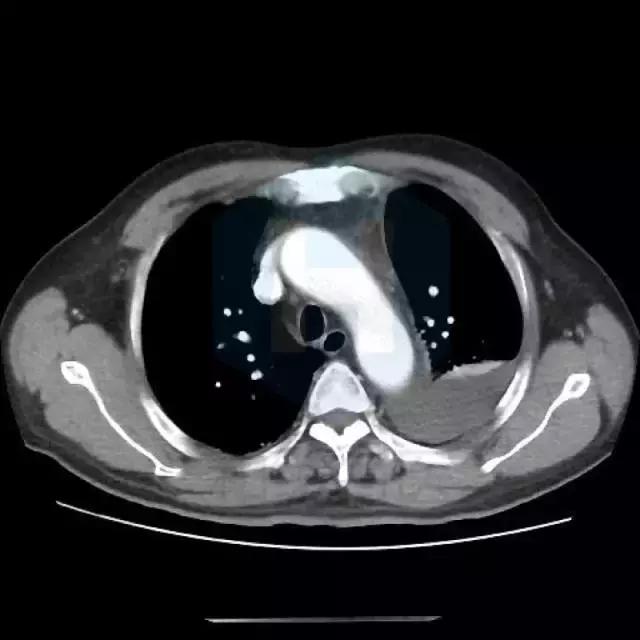

从CT来看,是比较典型的肺栓塞的表现,应该做肺动脉造影检查。

患者有胸痛,胸闷,1型呼吸衰竭,胸部影像示左下肺为“三角形”肺实变影伴胸腔积液,高度怀疑存在肺栓塞,建议行CTPA检查和肺核素通气/灌注现象检查。同时需排除肺栓塞原因,如肿瘤,自身免疫性疾病等。肺栓塞也会有黄疸和溶血表现。 胸痛特点和表现不符合心绞痛,左侧胸腔积液与左侧肺部病变有关。 患者黄疸考虑为溶血性黄疸,应行查找溶血原因,此外,血红蛋白有下降,便潜血阳性,有同时伴有失血可能,建议查血网织红细胞计数评价贫血情况,应行胃肠镜检查以明确消化道出血原因。 目前低价血症原因考虑不除外副肿瘤综合症可能,注意纠正电解质紊乱。 可视医院条件,建议安排下一步检查:胸部增强CT及CTPA,或肺通气/灌注检查,下肢及深静脉超声,血肿瘤标志物,血网织红细胞计数,自身免疫抗体(ANA,ENA,ANCA)等,胃肠镜检查。 由于目前有消化道出血风险,暂不建议抗凝治疗。密切观察。